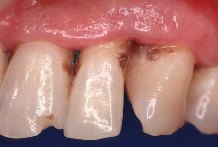

La gingivitis, es la inflamaci�n superficial de las enc�as causada por irritantes de las bacterias presentes en la boca (placa dental o bacteriana), y es com�n en todas las edades, incluyendo en escolares.

La

periodontitis, que normalmente se denomina "piorrea" (en griego "flujo de

pus"), incluye la inflamaci�n cr�nica y destrucci�n del hueso que soporta los

dientes. Tambi�n, las fibras gingivales y el ligamento periodontal son destruidos y el

borde de las enc�as se desprende de los dientes, formando lo que se llama una bolsa

periodontal en la cual puede aparecer pus. La bolsa periodontal se agranda si el hueso es

destruido m�s severamente y, en consecuencia, los dientes "se aflojan". Al

avanzar la enfermedad los dientes se pueden mover a�n m�s y es frecuente que se forme un

absceso e incluso que se caigan.